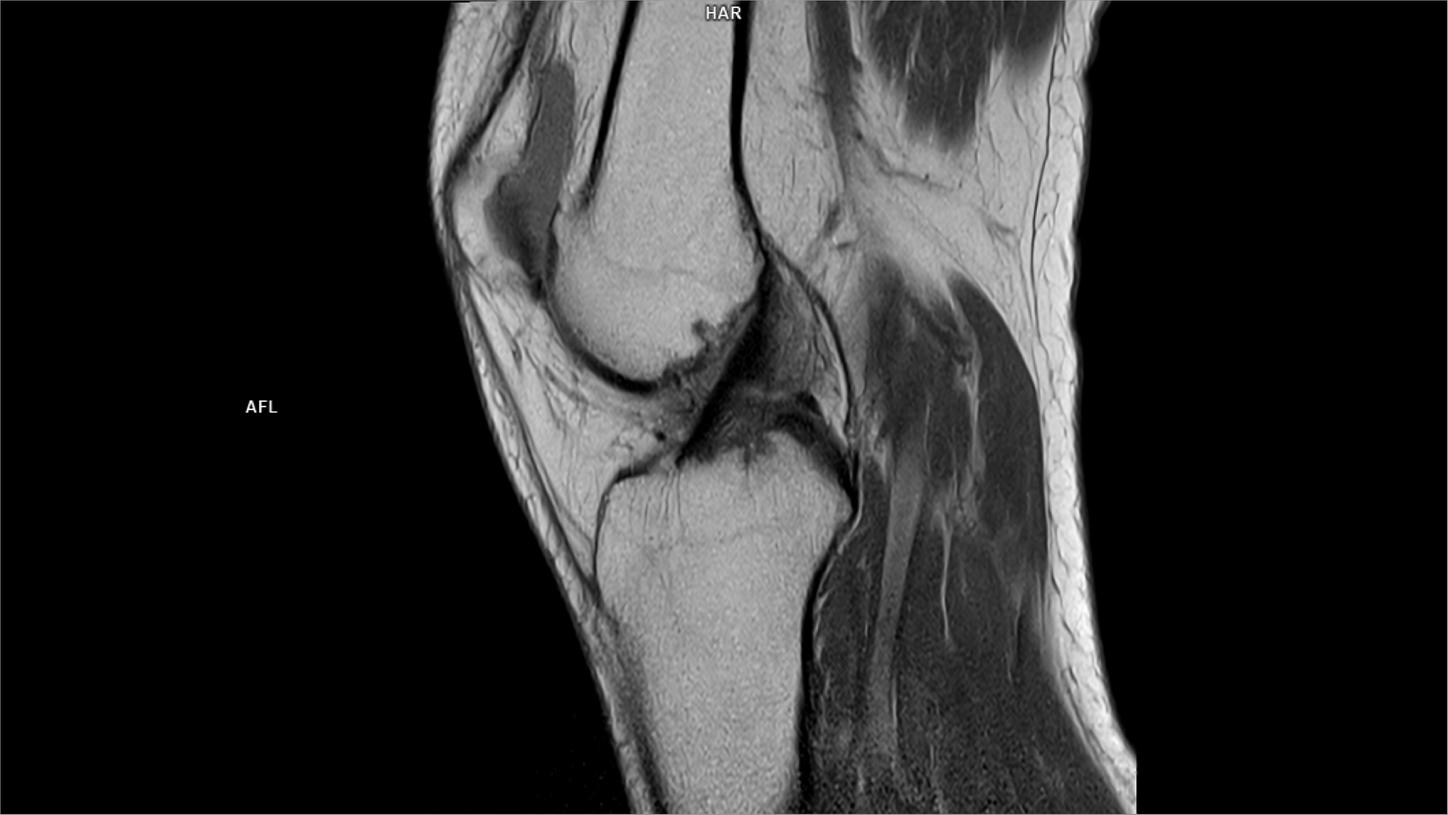

Sagittal PD-MAGNETOM Free.Max

04/07/2022

Coil-Contour Small x2/Resolution-704/Scan Time-4:08/Aceleration-s2 DRS